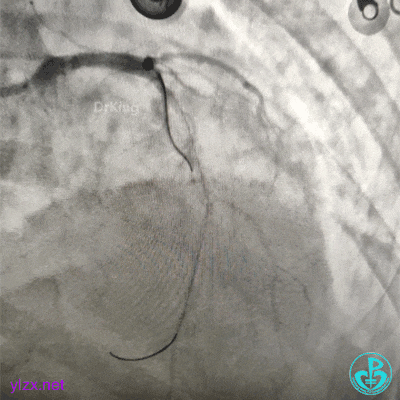

血压低,去甲肾上腺素8mg,25ml/h微量泵入,血压高时可维持在140/80mmHg左右,一直到手术结束。

交换导丝后扩支架网眼。

结束手术。

下台时血压127/78mmHg,心率75次/分。